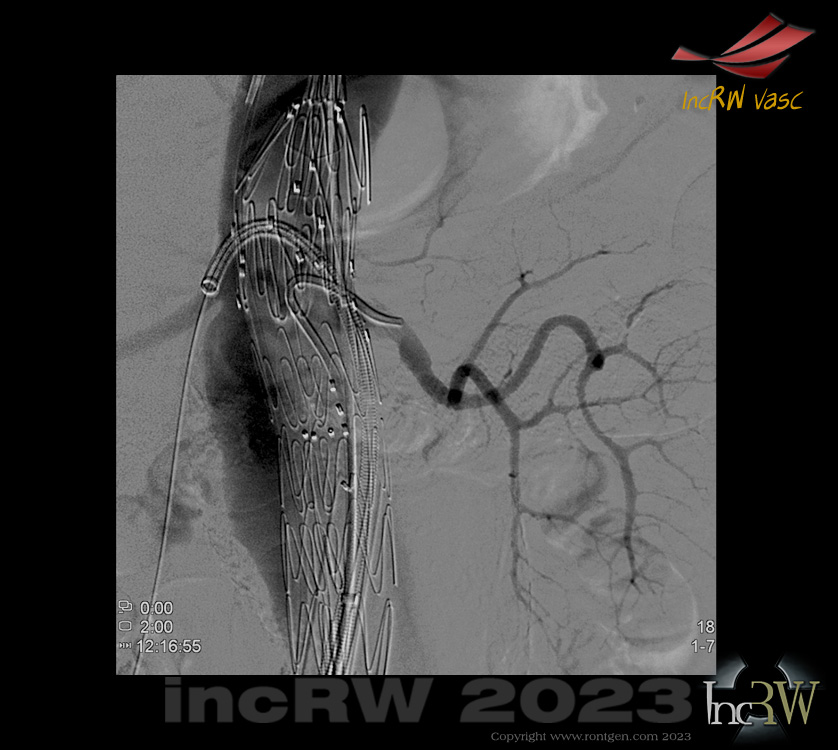

FEVAR utlösta njurgrafter Efter vidgning med CODA-ballong expanderas varje graft efterhand i de olika visceralkärlen.

- Varje visceral-graft efterdilateras efter resp. deponering med PTA ballong 10×20, 80cm (ny PTA-ballong till varje graft) som löper över Storq-ledaren in i resp. sidoartär.